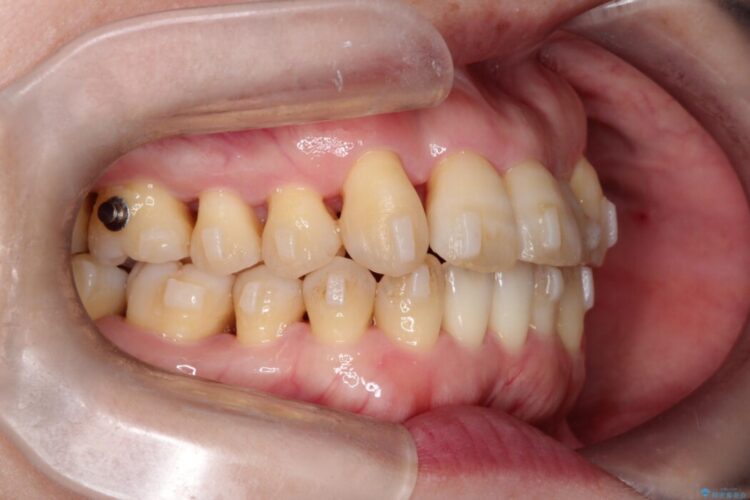

検査をしたところ噛み合わせのズレに加えて歯周病も併発していました。

よって歯牙への負担が少なくなるように慎重に治療計画を立てました。

まずは歯周病の治療に専念し、その後インビザラインの矯正治療へ移ることとしました。

本症例では歯周治療に半年ほど時間をかけています。